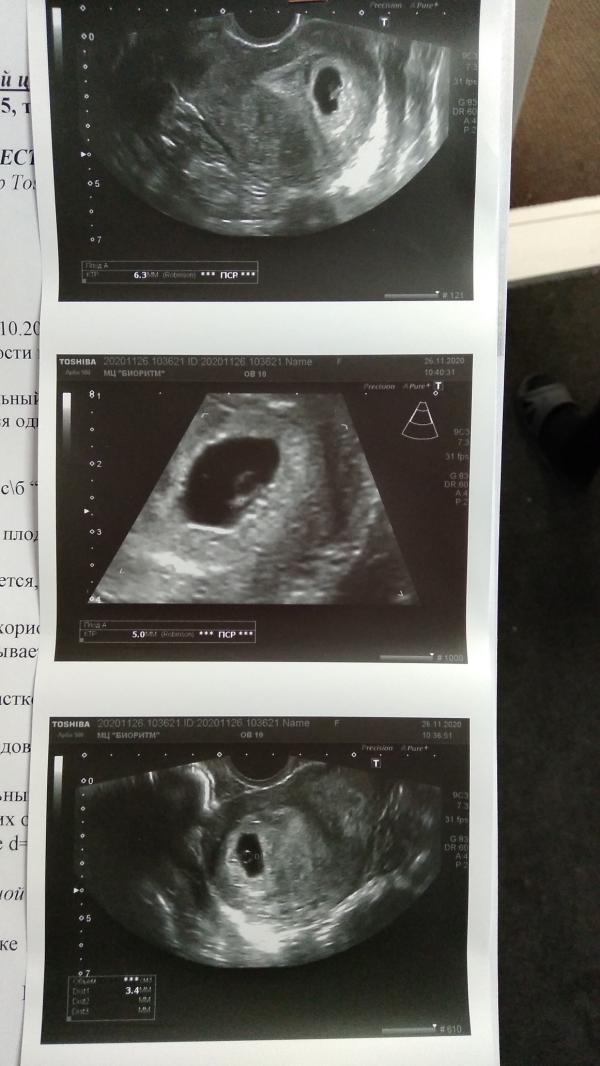

Сходила я на УЗИ,у меня 6 недель, правда сердцебиение не в норме на таком сроке,гораздо меньше. Он такой маленький,врач дала время на раздумья,пока анализы и прочее,в запасе полторы недели грубо говоря. Буду думать

Какие показатели сердцебиения? У вас цикл стабильный всегда, стандартный?

@calimaiel1990 да, СБ низкое.. посоветую переделать УЗИ через неделю, можно не полностью все размеры плода, а только чтобы СБ глянули. У меня перед замиранием СБ было низкое..((